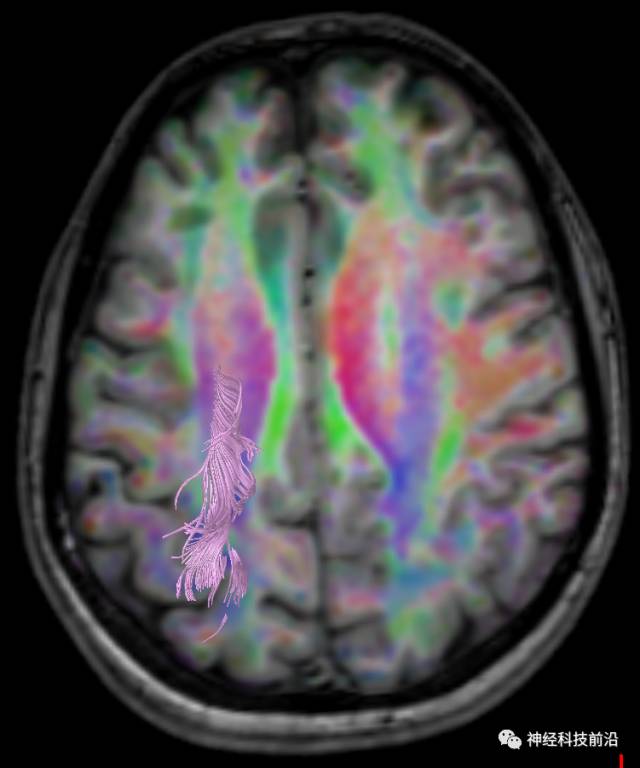

皮质脊髓束与皮质脑桥束的关系毗邻

脑干内高信号为一近环形纤维束,其作用尚待研究。

上述纤维束与小脑中脚的位置毗邻